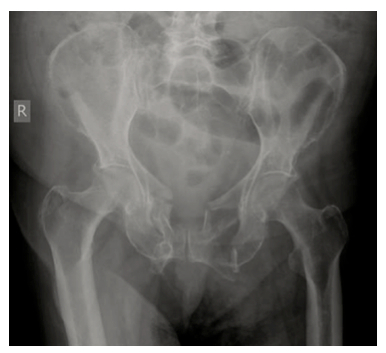

The Bind When It Comes to a Binder (Part 3)

There’s been a lot of stimulating discussion after parts 1 and 2 of this series from Dr Alan Garner (you can check those here and here). Here’s part 3. Thanks for sticking with the discussion so far. In part 2 we had a look at AP compression injuries and lateral compression…

The Bind About Pelvic Binders (Part 2)

This is part 2 in Dr Alan Garner’s series on pelvic fractures and the approach to binders. You can find part 1 here. In part one we had a look at the evidence for benefit from pelvic binders. In short there is no study yet published showing a significant improvement…

The Bind When it Comes to Using a Binder

This post by Dr Alan Garner is the first of a trio on the topic of pelvic fractures and the evidence for what to do. Alan is an emergency physician at Nepean Hospital in Sydney and the Medical Director of CareFlight, having started in prehospital medicine in 1996. He has…